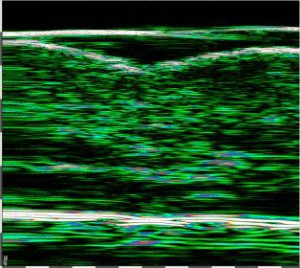

-Υπέρηχος Υψηλής Συχνότητας (HFUS) και Ιστολογία